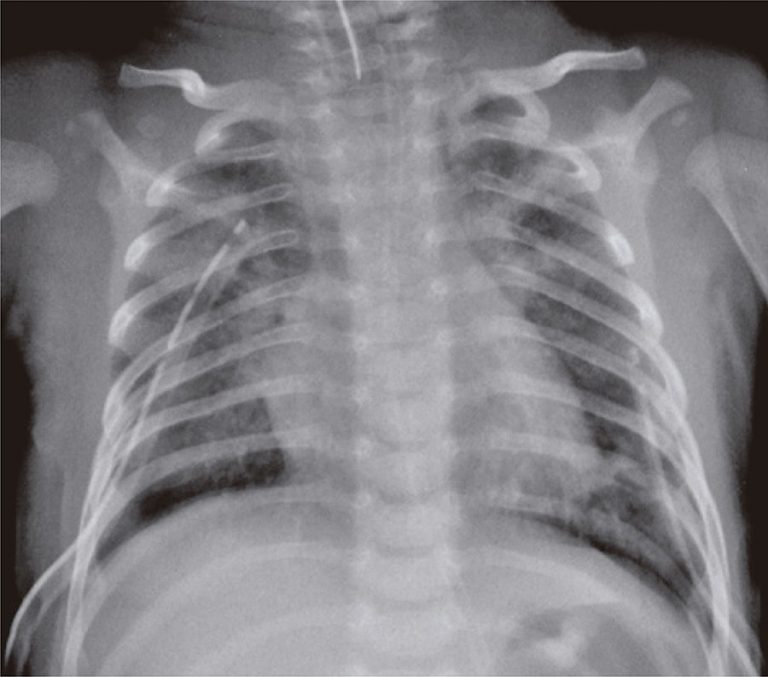

A 37-days-old baby boy, previously healthy and without intercurrences during perinatal period, who was admitted in pediatric intensive care unit with acute ventilator insufficiency because of viral bronchiolitis due to respiratory syncytial virus. The patient underwent a tracheal intubation by clinical deterioration, a rapid sequence intubation using fentanyl, ketamine and succinylcholine. During the procedure, he had cough, chest rigidity, reduction of respiratory sounds and poor tissue perfusion. His clinical picture worsened and resulted in cardiorespiratory arrest in asystole that was reverted with chest compressions and two doses of intravenous epinephrine. Subsequently, the patient showed a new cardiorespiratory arrest, and he was under risk for hypertensive pneumothorax. A relief thoracentesis was carried out and significant improvement was observed in respiratory sound and signs of poor peripheral perfusion. After bilateral thoracic drainage the patient had ventilator parameters reduced, however, this reduction remained with impaired tissue perfusion, mottled skin, fine pulses, hypotension, and cardiac auscultation with hypophonesis sound. The chest radiology exam confirmed hypertensive pneumopericardium () that resolved with pericardiocenthesis and drainage of 40mL of pericardium air space (). The patient had good clinical progress after underwent the procedure, remained in mechanical ventilation for 6 days, and he was discharged 13 days after the procedure without apparent sequelae.